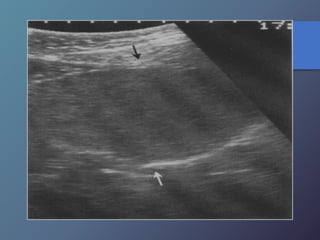

Traumatismo Hepático

• La lesión hepática es a predominio del lóbulo derecho.

• Mayor particularidad en segmento posterior.

• Mayor frecuencia por laceración peri vascular.

• Se producen hematomas subcapsulares,

pericapsulares o aislados.

• La hemorragia en las primeras 24 horas es ecogénica y

posteriormente se hace mas hipoecogénica.

• Entre las dos o tres semanas se puede observar gran

cantidad tejido de granulación.